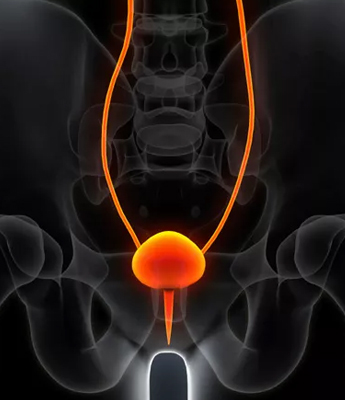

The prostate gland is a small, walnut-sized exocrine gland located at the base of the bladder. It plays a vital role in the male reproductive system by producing a significant portion of semen and providing nourishment to sperm, essential for their transport and protection during ejaculation. Disorders of the prostate, which are common in men over the age of 45, can significantly impact prostate function and overall health. Conditions such as Benign Prostatic Hyperplasia (BPH) cause the prostate to enlarge and may lead to urinary difficulties, while Prostatitis, an inflammation often resulting from infections or other causes, can produce symptoms like pelvic pain and urinary discomfort.

Prostate Cancer, a serious condition involving the development of cancerous cells in the prostate, is another critical concern. Regular consultations with a urologist are crucial for maintaining prostate health. Urologists provide valuable screenings, expert advice, and tailored treatment recommendations to address prostate disorders effectively. Early detection and management of these conditions are essential for preserving quality of life and ensuring optimal prostate function.